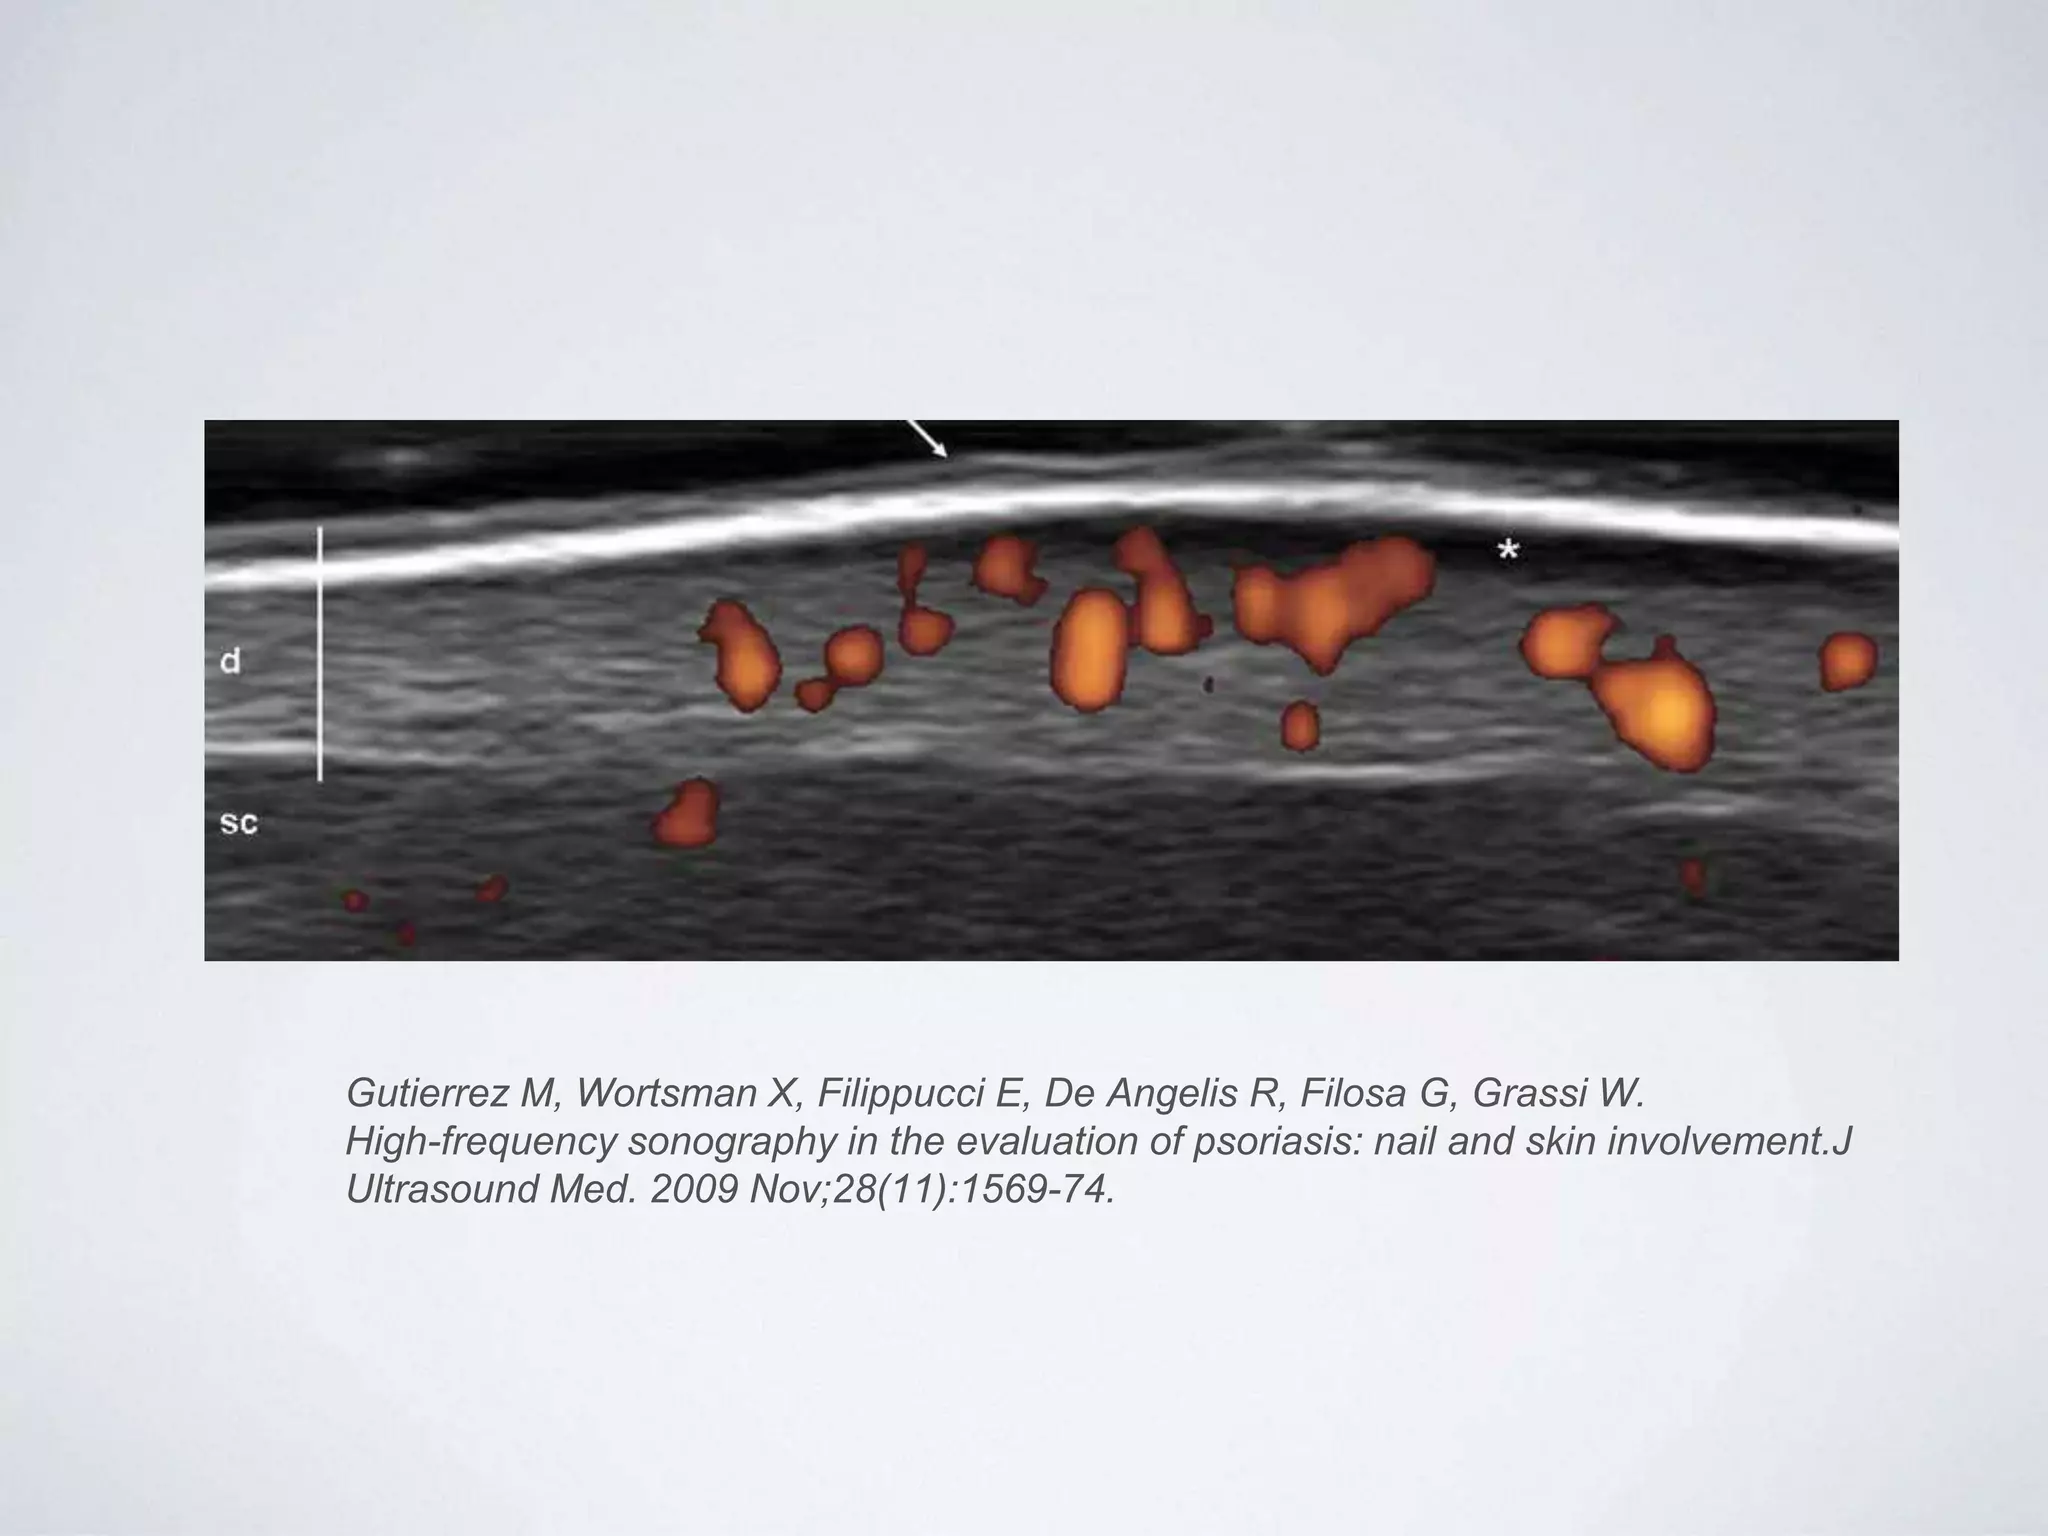

Gutierrez M, Wortsman X, Filippucci E, De Angelis R, Filosa G, Grassi W.

High-frequency sonography in the evaluation of psoriasis: nail and skin involvement.J

Ultrasound Med. 2009 Nov;28(11):1569-74.

Características ecográficas

de la psoriasis ungueal

• Engrosamiento de la tabla

ungueal de manera focal o

generalizada

• Ondulación ventral de la

tabla ungueal

• Aumento grosor del lecho

ungueal

• Aumento de flujo en lecho

ungueal y posiblemente en

el área perimatricial.